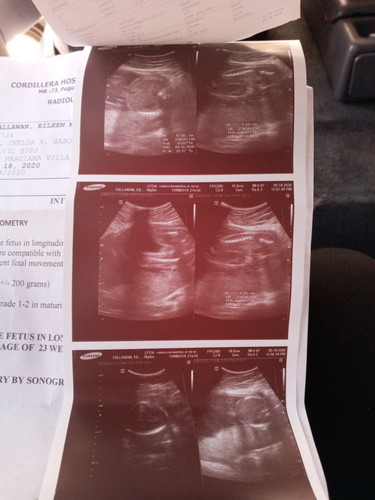

its a BOY!!!!